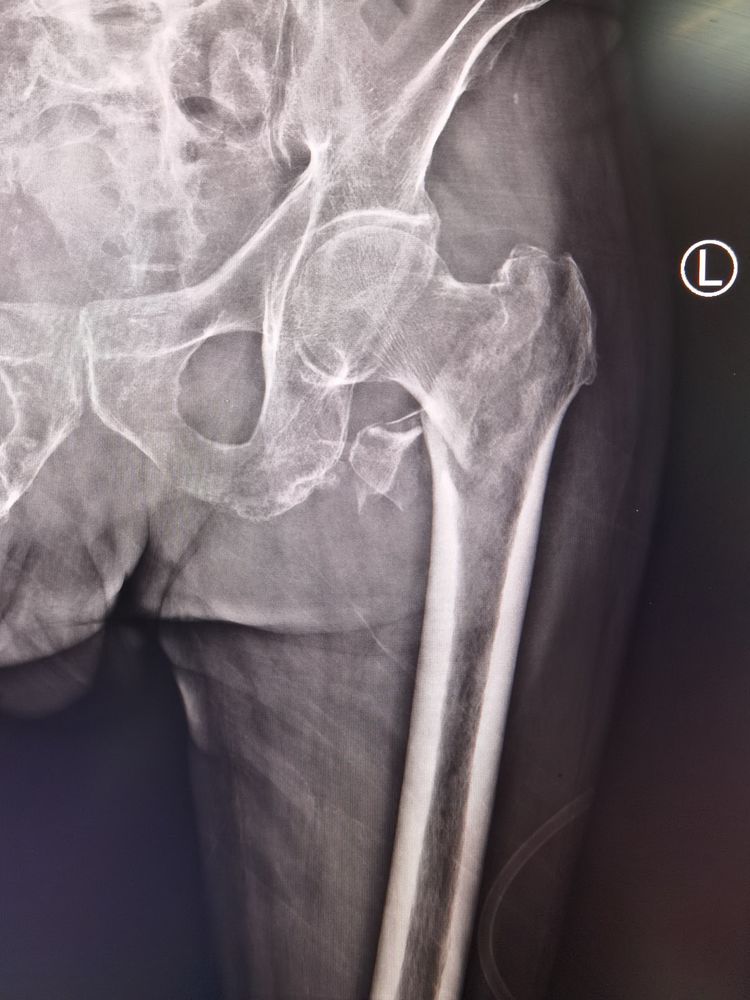

患者81岁高龄男性,因反复胸闷、气短3年,于省级三甲医院诊断为“难治性心力衰竭”,并多次住院治疗,长期口服抗心衰药物控制病情;2020.8.2患者不慎摔伤,就近三甲医院住院,诊断为“左侧股骨粗隆间骨折”,考虑患者病情危重,期间多次会诊后不予安排手术治疗;故于2020.8.11转至我院心血管二病区,由卢玉俊副主任医师团队收治,诊断为:慢性心力衰竭急性加重、心功能Ⅳ级,左侧股骨粗隆间骨折,双侧胸腔积液并双肺下叶膨胀不全,多处Ⅲ期压疮。经过卢玉俊副主任医师团队的精心治疗后患者内科症状得到一定改善;为进一步控制患者病情,由麻醉手术科冯秀玲主任牵头,关节外科曾昭洋主任及ICU王煜主任共同会诊后,进行充分论证,精心准备,于2020.8.22上午9时患者接入手术室,由于患者有严重的腰椎侧弯畸形,增加麻醉难度,由冯秀玲主任亲自为患者实施椎管内麻醉,待麻醉成功后,患者出现房颤,心率很快由70上升至120次左右,在冯秀玲主任医师麻醉团队有条不紊地对症治疗下,患者心率得到控制;接下来由曾昭洋主任医师团队闭合复位左侧股骨粗隆间骨折,C臂透视下实施PFNA内固定术,手术历时30分钟,骨折断端复位满意,内固定牢靠,术后转至我院重症医学科(ICU),由王昱主任医师ICU团队接手继续患者术后治疗,目前患者病情在ICU医师团队的密切治疗下,术后恢复良好。

术前